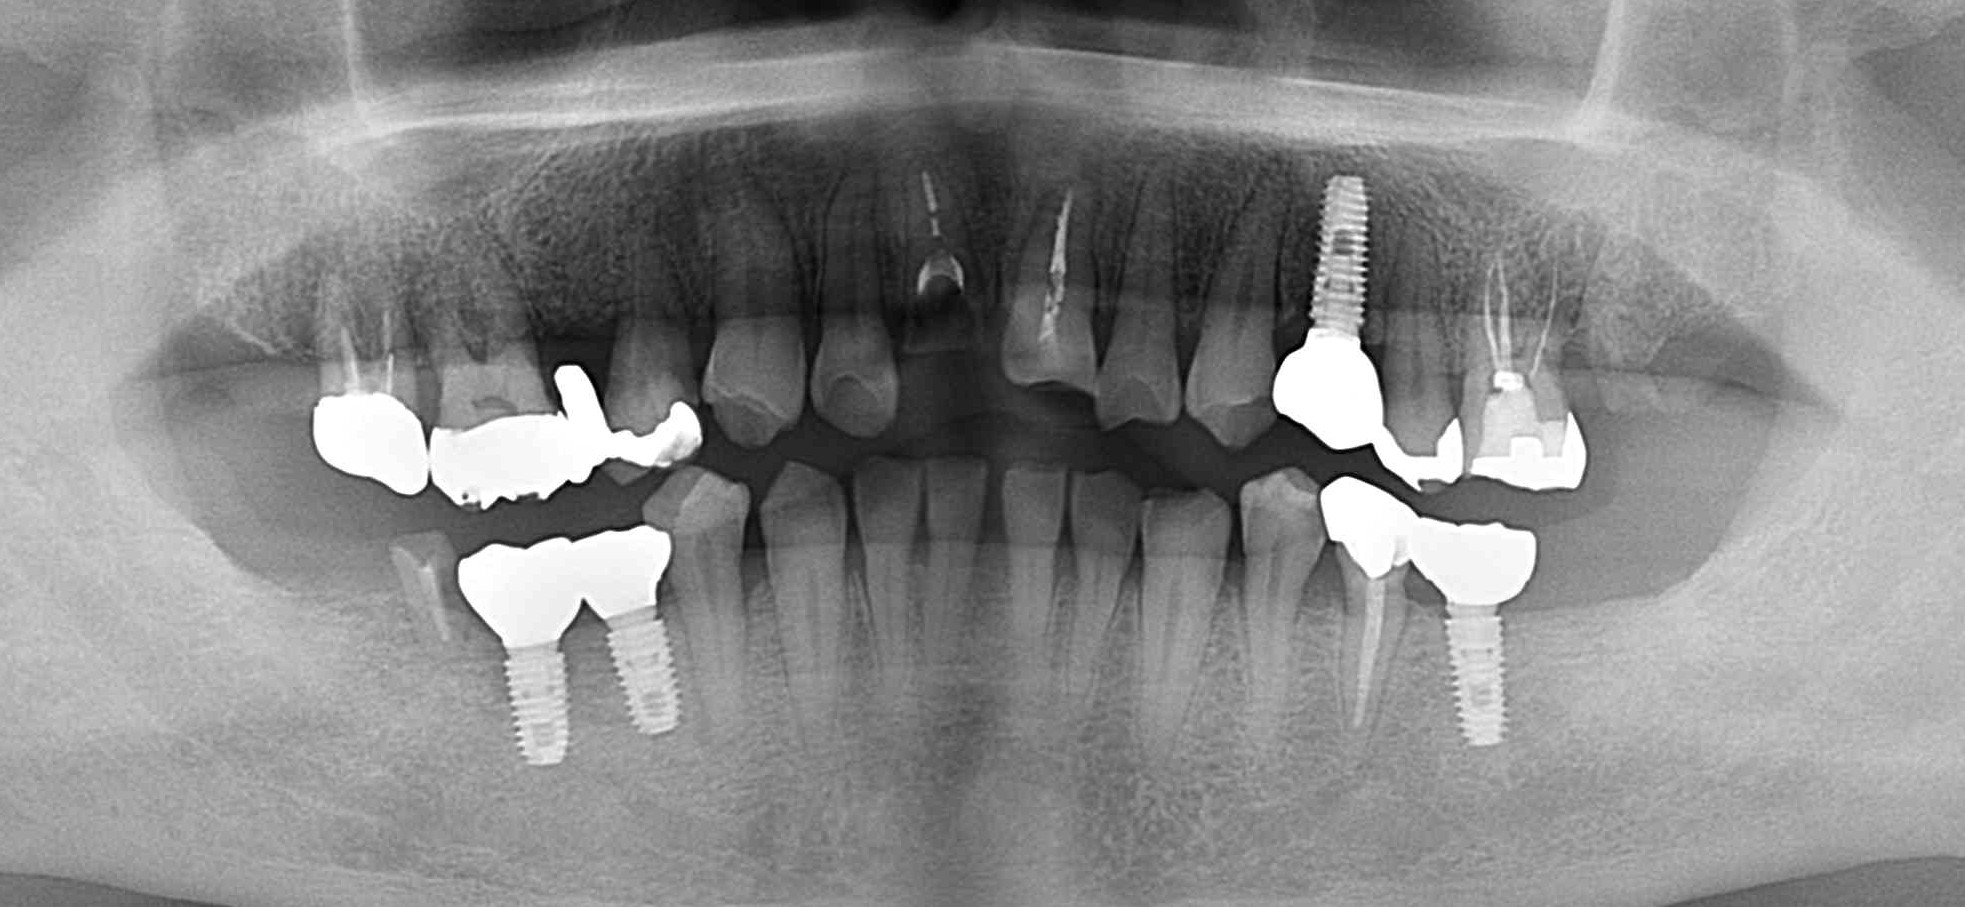

インプラント症例

Before

After

| 年齢・性別 | 59歳・男性 |

|---|---|

| 治療期間・回数 | 約7か月 |

| 治療方法 | インプラント埋入 上部構造 骨造成 |

| 費用 | インプラント埋入:200,000×5 上部構造:100,000×5 骨造成:30,000 合計:1,530,000円×Tax |

| 備考 | クロスバイトが所々あり、奥歯が崩壊しているのは咬合が強い方と思われました。 ナイトガードせず数年経過していますが、経過良好です。 |